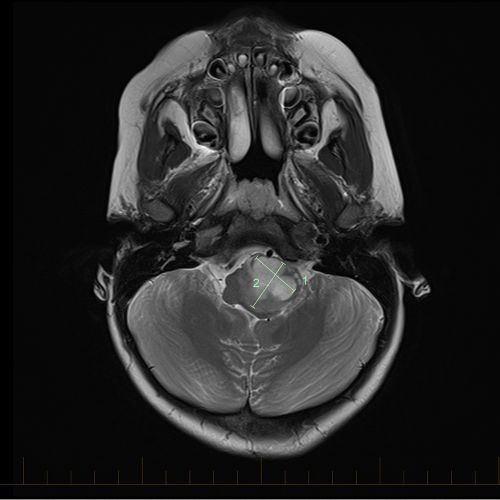

X Ray Multiple Part Of Child S Body Multiple Disease Stroke Brain Tumor Rheumatoid Arthritis Sinusitis Gouty Arthritis Etc Skull Chest Lung Heart Spine Arm Hand